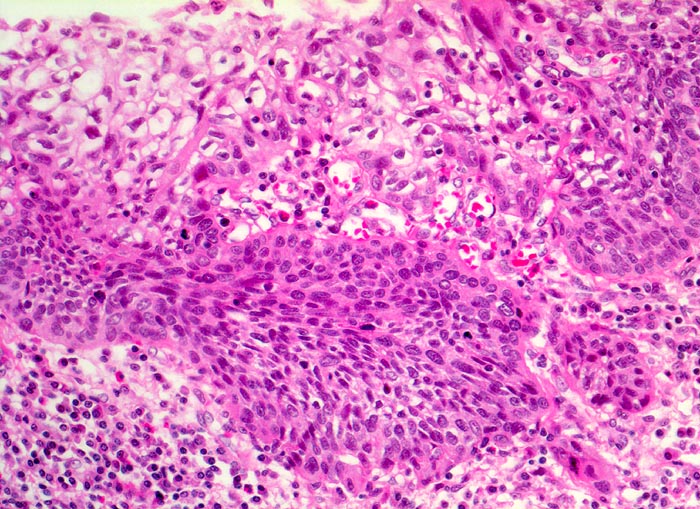

Carcinoma in situ der Ösophagusschleimhaut mit beginnender Invasion

Das schwer dysplastische Epithel bildet unregelmässige Zapfen, die in das Stroma vordringen. Fährt man an der Basis entlang, erkennt man an einer Stelle eine zipflige Tumorinvasion des Stromas. An dieser Stelle ist keine Basalmembran erkennbar. Die Submukosa enthält ein dichtes gemischtes Entzündungsinfiltrat.

Jahrelanger Nikotin- und Ethylabusus. Vor 6 Monaten ergab die Abklärung wegen progredienter Dysphagie ein inoperables stenosierendes Karzinom im distalen Ösophagus. Der Patient verstirbt am Tumorleiden.

Histologie

200